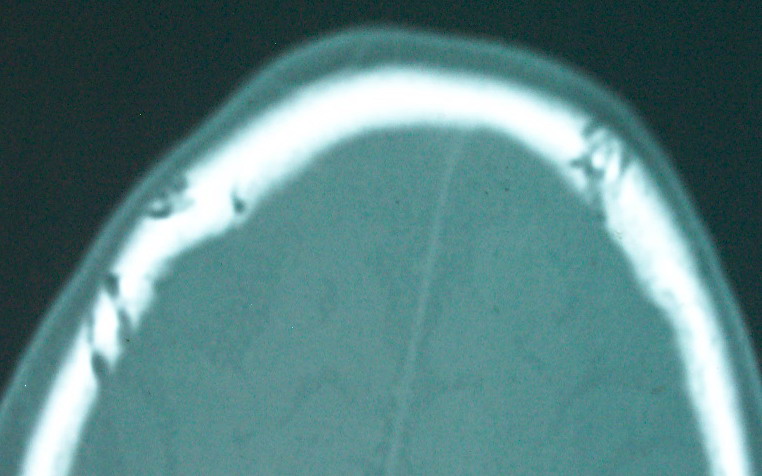

以下是引用余辉在2009-4-15 20:49:00的发言:[br]右侧病灶发生于冠状缝区,但额骨左侧鳞也有病灶,病灶区脑沟裂增宽(有脑萎缩征像,把这个征像放在颅骨病变一起考虑可能有点牵强),是否可能是板障血管畸形所致谢?抑或是嗜酸性肉芽肿或蛛网膜粒压迹那类东西?

以下是引用whzht在2009-4-15 20:57:00的发言:[br]1、额骨改变,考虑蛛网膜粒压迹;[br]2、脑萎缩。